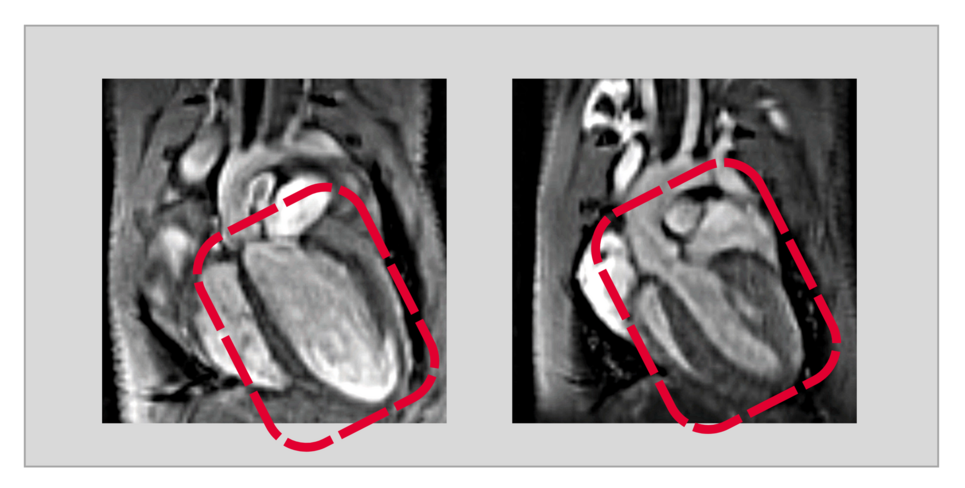

Die Bad Nauheimer Wissenschaftlerinnen stellten nun in Experimenten in einem Mausmodell fest, dass niedrige USP5-Spiegel eine dilatative Kardiomyopathie auslösen.

„Durch einen gentechnischen Eingriff konnten wir in den Herzmuskelzellen ausgewachsener Tiere USP5 gezielt ausschalten. Fehlte dann das USP5, entwickelte sich in der Folge eine dilatative Kardiomyopathie“, berichtet Silke Kreher. Co-Autorin Yvonne Eibach fügt hinzu: „Mit Hilfe der Magnetresonanztomographie als Bildgebungsverfahren konnten wir eindrucksvoll nachweisen, dass bei diesen Tieren das gesamte Herz deutlich vergrößert und die Pumpleistung stark eingeschränkt ist.“